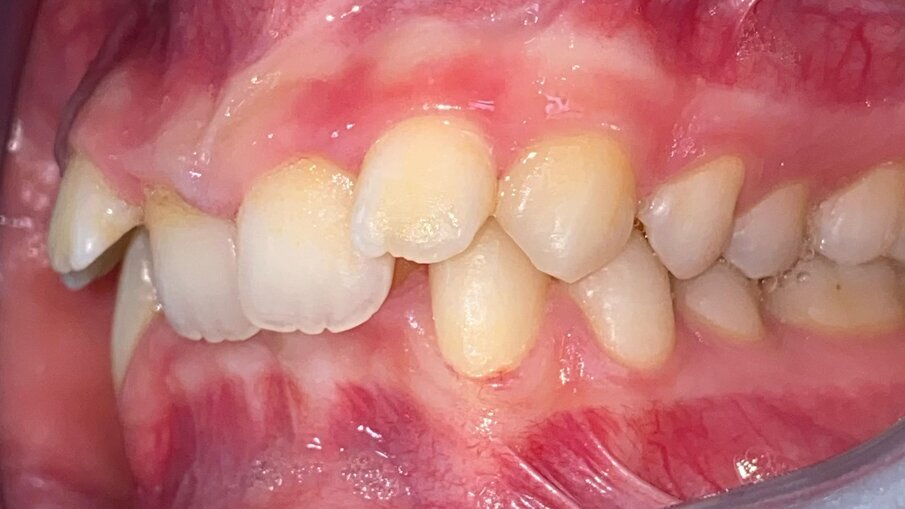

All’esame obiettivo intraorale si riscontra sul piano frontale un severo morso profondo con precontatto traumatico degli incisivi superiori contro la papilla retroincisiva e le rughe palatine anteriori durante la massima intercuspidazione, con overbite di 10 mm (Fig. 5). Dalle foto laterali si evidenzia una malocclusione di Classe II divisione 2 con scissor bite dell’elemento 1.5 (Figg. 6, 7), mentre dalle foto occlusali si rileva un grave affollamento con contrazione di entrambe le arcate maggiore nella zona premolare (Figg. 8, 9). L’analisi di Bolton mostra un eccesso superiore 3-3 di 2,34 mm (73,6%) e 6-6 di 2,76 mm (88,8%). L’analisi cefalometrica evidenzia una Classe II scheletrica, modello facciale normodivergente, angolo interincisale aumentato, incisivi superiori e inferiori retroinclinati (Fig. 10). La radiografia panoramica mostra la presenza dei germi dei terzi molari, assenza di parallelismo tra le radici dei premolari inferiori (Fig. 11) e una sovraeruzione degli incisivi inferiori che crea un doppio piano tra gli incisivi e i molari, segno di una curva di Spee molto profonda.

Fig. 6_Laterale destra pre-trattamento.